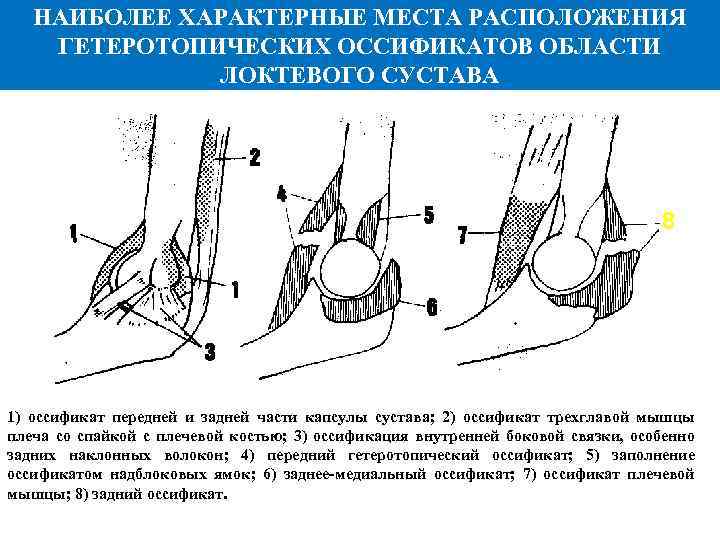

НАИБОЛЕЕ ХАРАКТЕРНЫЕ МЕСТА РАСПОЛОЖЕНИЯ ГЕТЕРОТОПИЧЕСКИХ ОССИФИКАТОВ ОБЛАСТИ ЛОКТЕВОГО СУСТАВА 8 1) оссификат передней и задней части капсулы сустава; 2) оссификат трехглавой мышцы плеча со спайкой с плечевой костью; 3) оссификация внутренней боковой связки, особенно задних наклонных волокон; 4) передний гетеротопический оссификат; 5) заполнение оссификатом надблоковых ямок; 6) заднее медиальный оссификат; 7) оссификат плечевой мышцы; 8) задний оссификат.

НАИБОЛЕЕ ХАРАКТЕРНЫЕ МЕСТА РАСПОЛОЖЕНИЯ ГЕТЕРОТОПИЧЕСКИХ ОССИФИКАТОВ ОБЛАСТИ ЛОКТЕВОГО СУСТАВА 8 1) оссификат передней и задней части капсулы сустава; 2) оссификат трехглавой мышцы плеча со спайкой с плечевой костью; 3) оссификация внутренней боковой связки, особенно задних наклонных волокон; 4) передний гетеротопический оссификат; 5) заполнение оссификатом надблоковых ямок; 6) заднее медиальный оссификат; 7) оссификат плечевой мышцы; 8) задний оссификат.